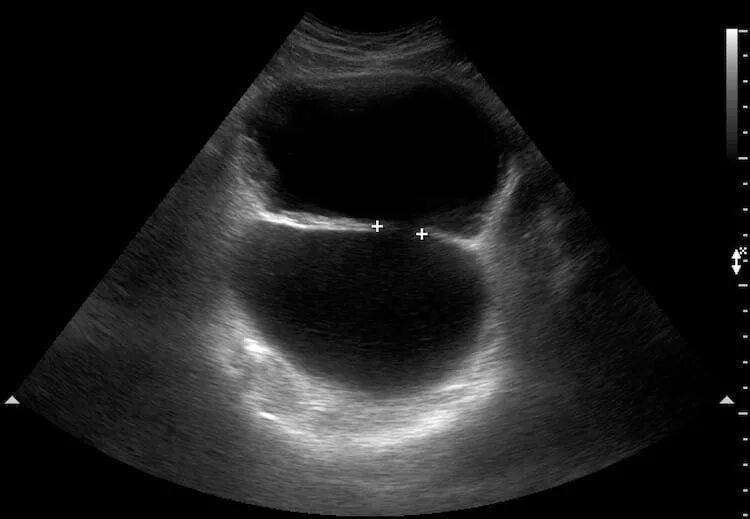

Дивертикул мочевого пузыря что это такое